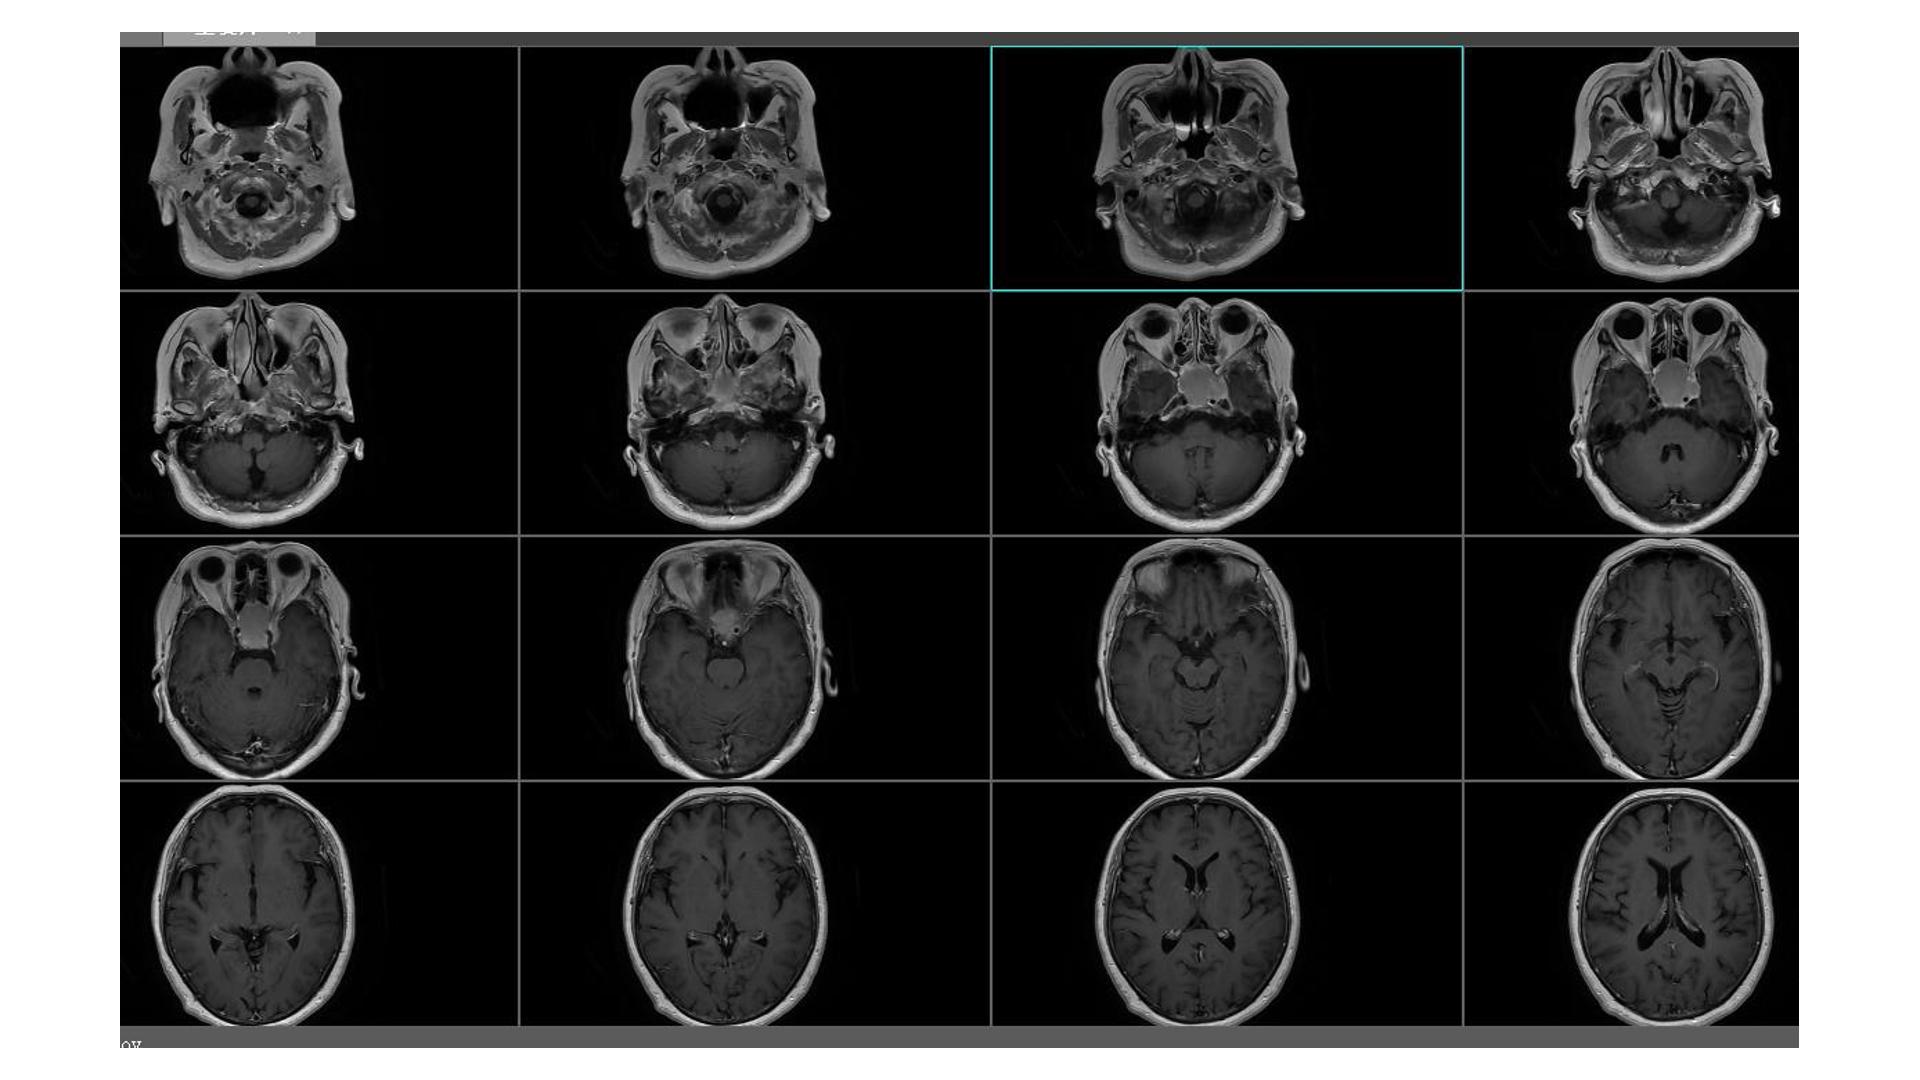

鞍区占位,蝶鞍扩大明显,侵袭海绵窦。